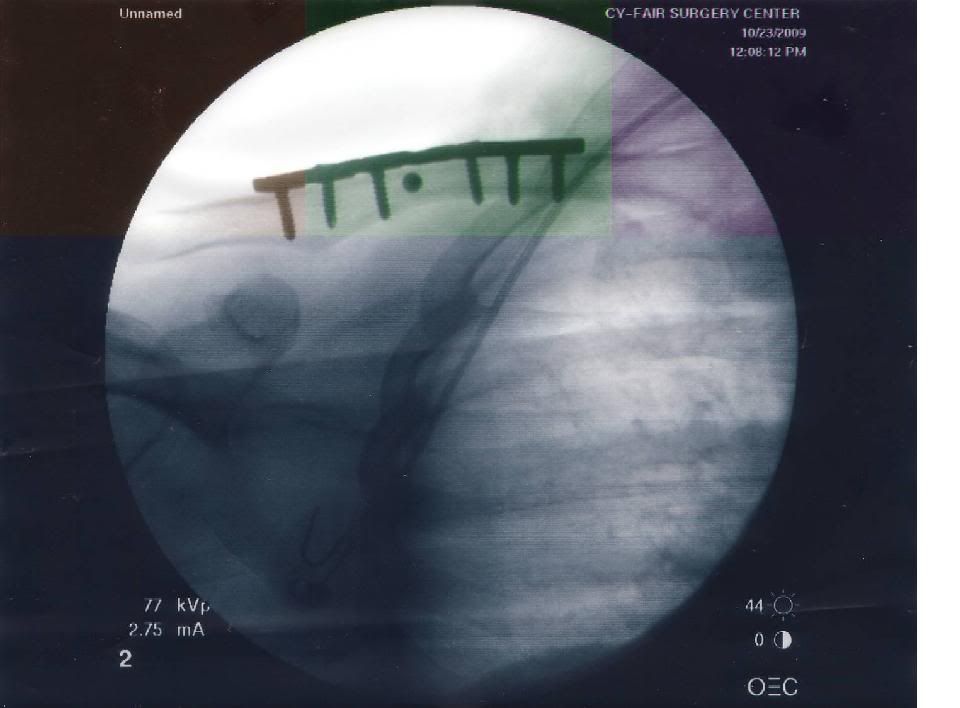

Pic of 6 Screws in shoulder - 10.25.2009, 08:43 PM

Here's the pic of the 6 screws put into my shoulder. A bit uncomfortable. I'm not taking any meds anymore, except over the counter tylenol. I kept having these weird dreams and whatnot.

Whats the dot between the 2 screws in the middle, JB Weld ?